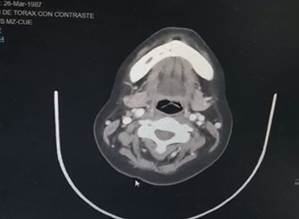

Among the auxiliary examinations of highlighted images presented, thickening of the mucosa in ethmoid cells, a radiolucent image in the upper palate (Figura 2), slight adenopathy at the retromandibular level (Figura 3), thickening of the mucosa of both maxillary sinuses, and thickening of the middle turbinate, there is a slight deviation to the left of the nasal septum (Figura 4), in the axial tomography of the head-lower part, a radiopaque image is appreciated in the left area of the palate, consistent with the necrosis evidenced in the physical examination , there is evidence of the presence of contrast hyper-uptake nodules and the presence of small adenopathies (Figura 5).

Figure 5. Axial head tomography, lower part, a radiopaque image is appreciated in the palate’s left area, consistent with the necrosis evidenced in the physical examination, the presence of hyper-contrast-uptake nodules, the presence of adenopathies.